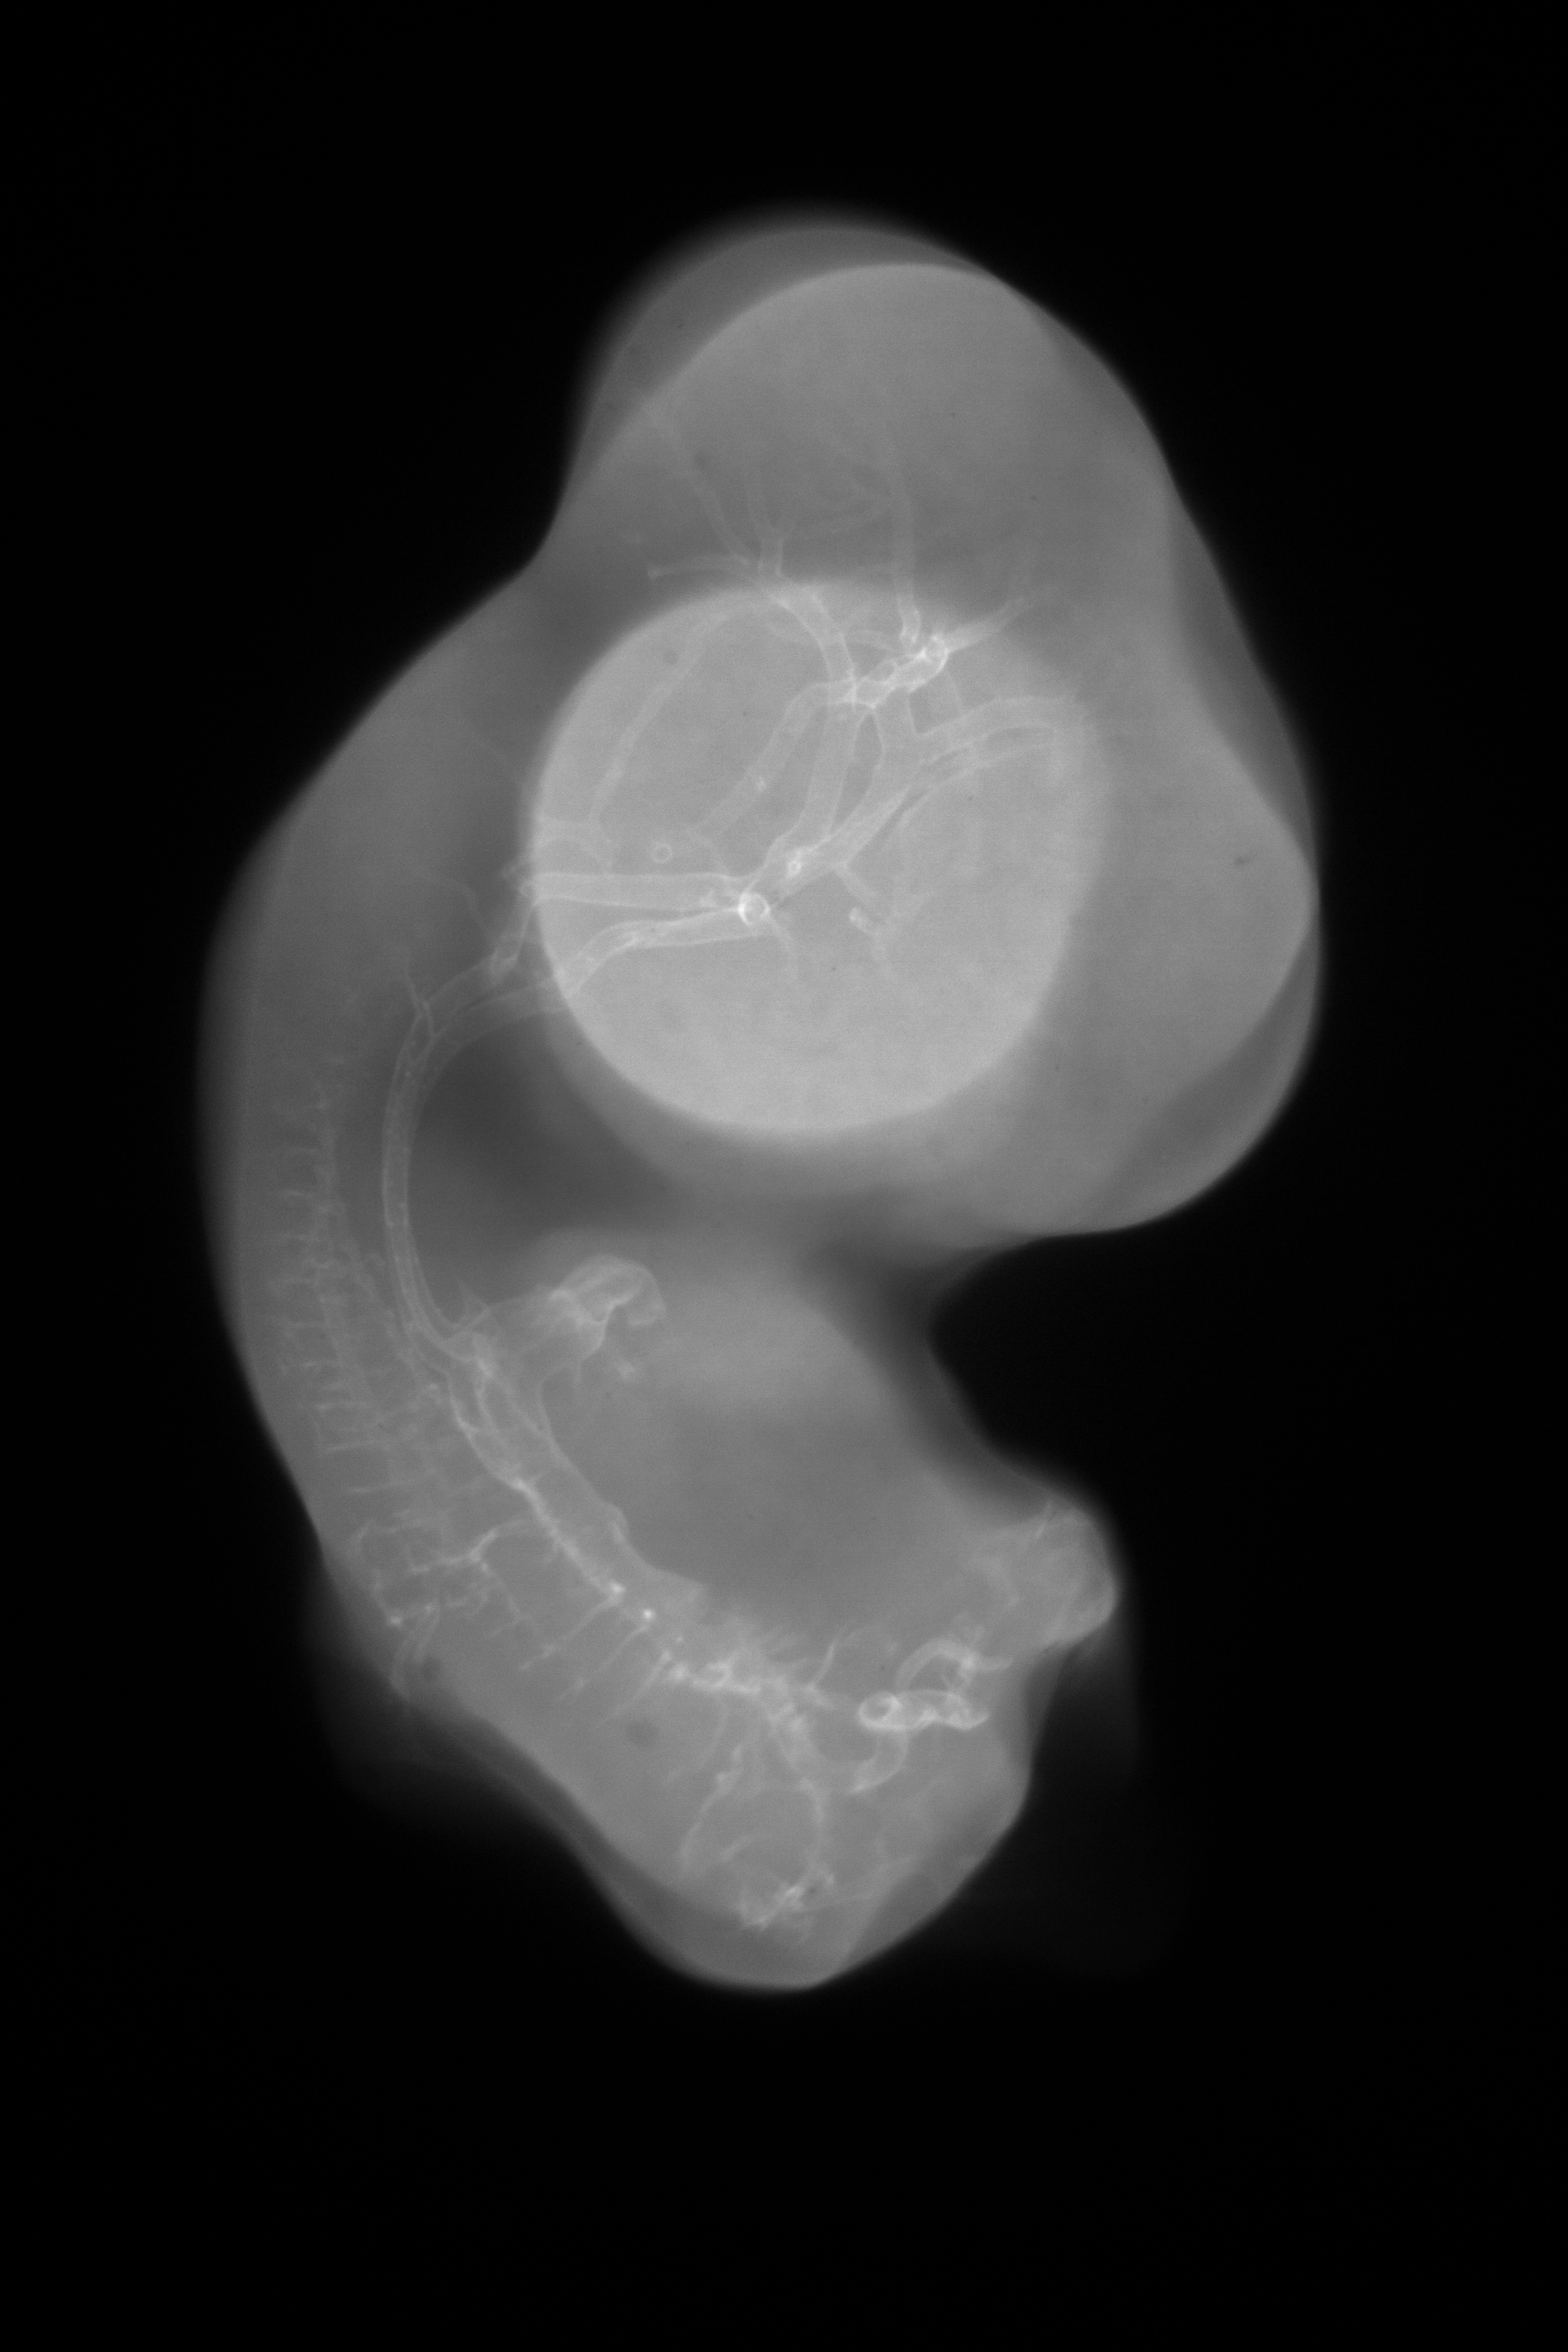

Chick Embryo Microangiography

Hamburger-Hamilton (HH) Stage 30 (approx. 6.5 days)

X-Ray Micrographs